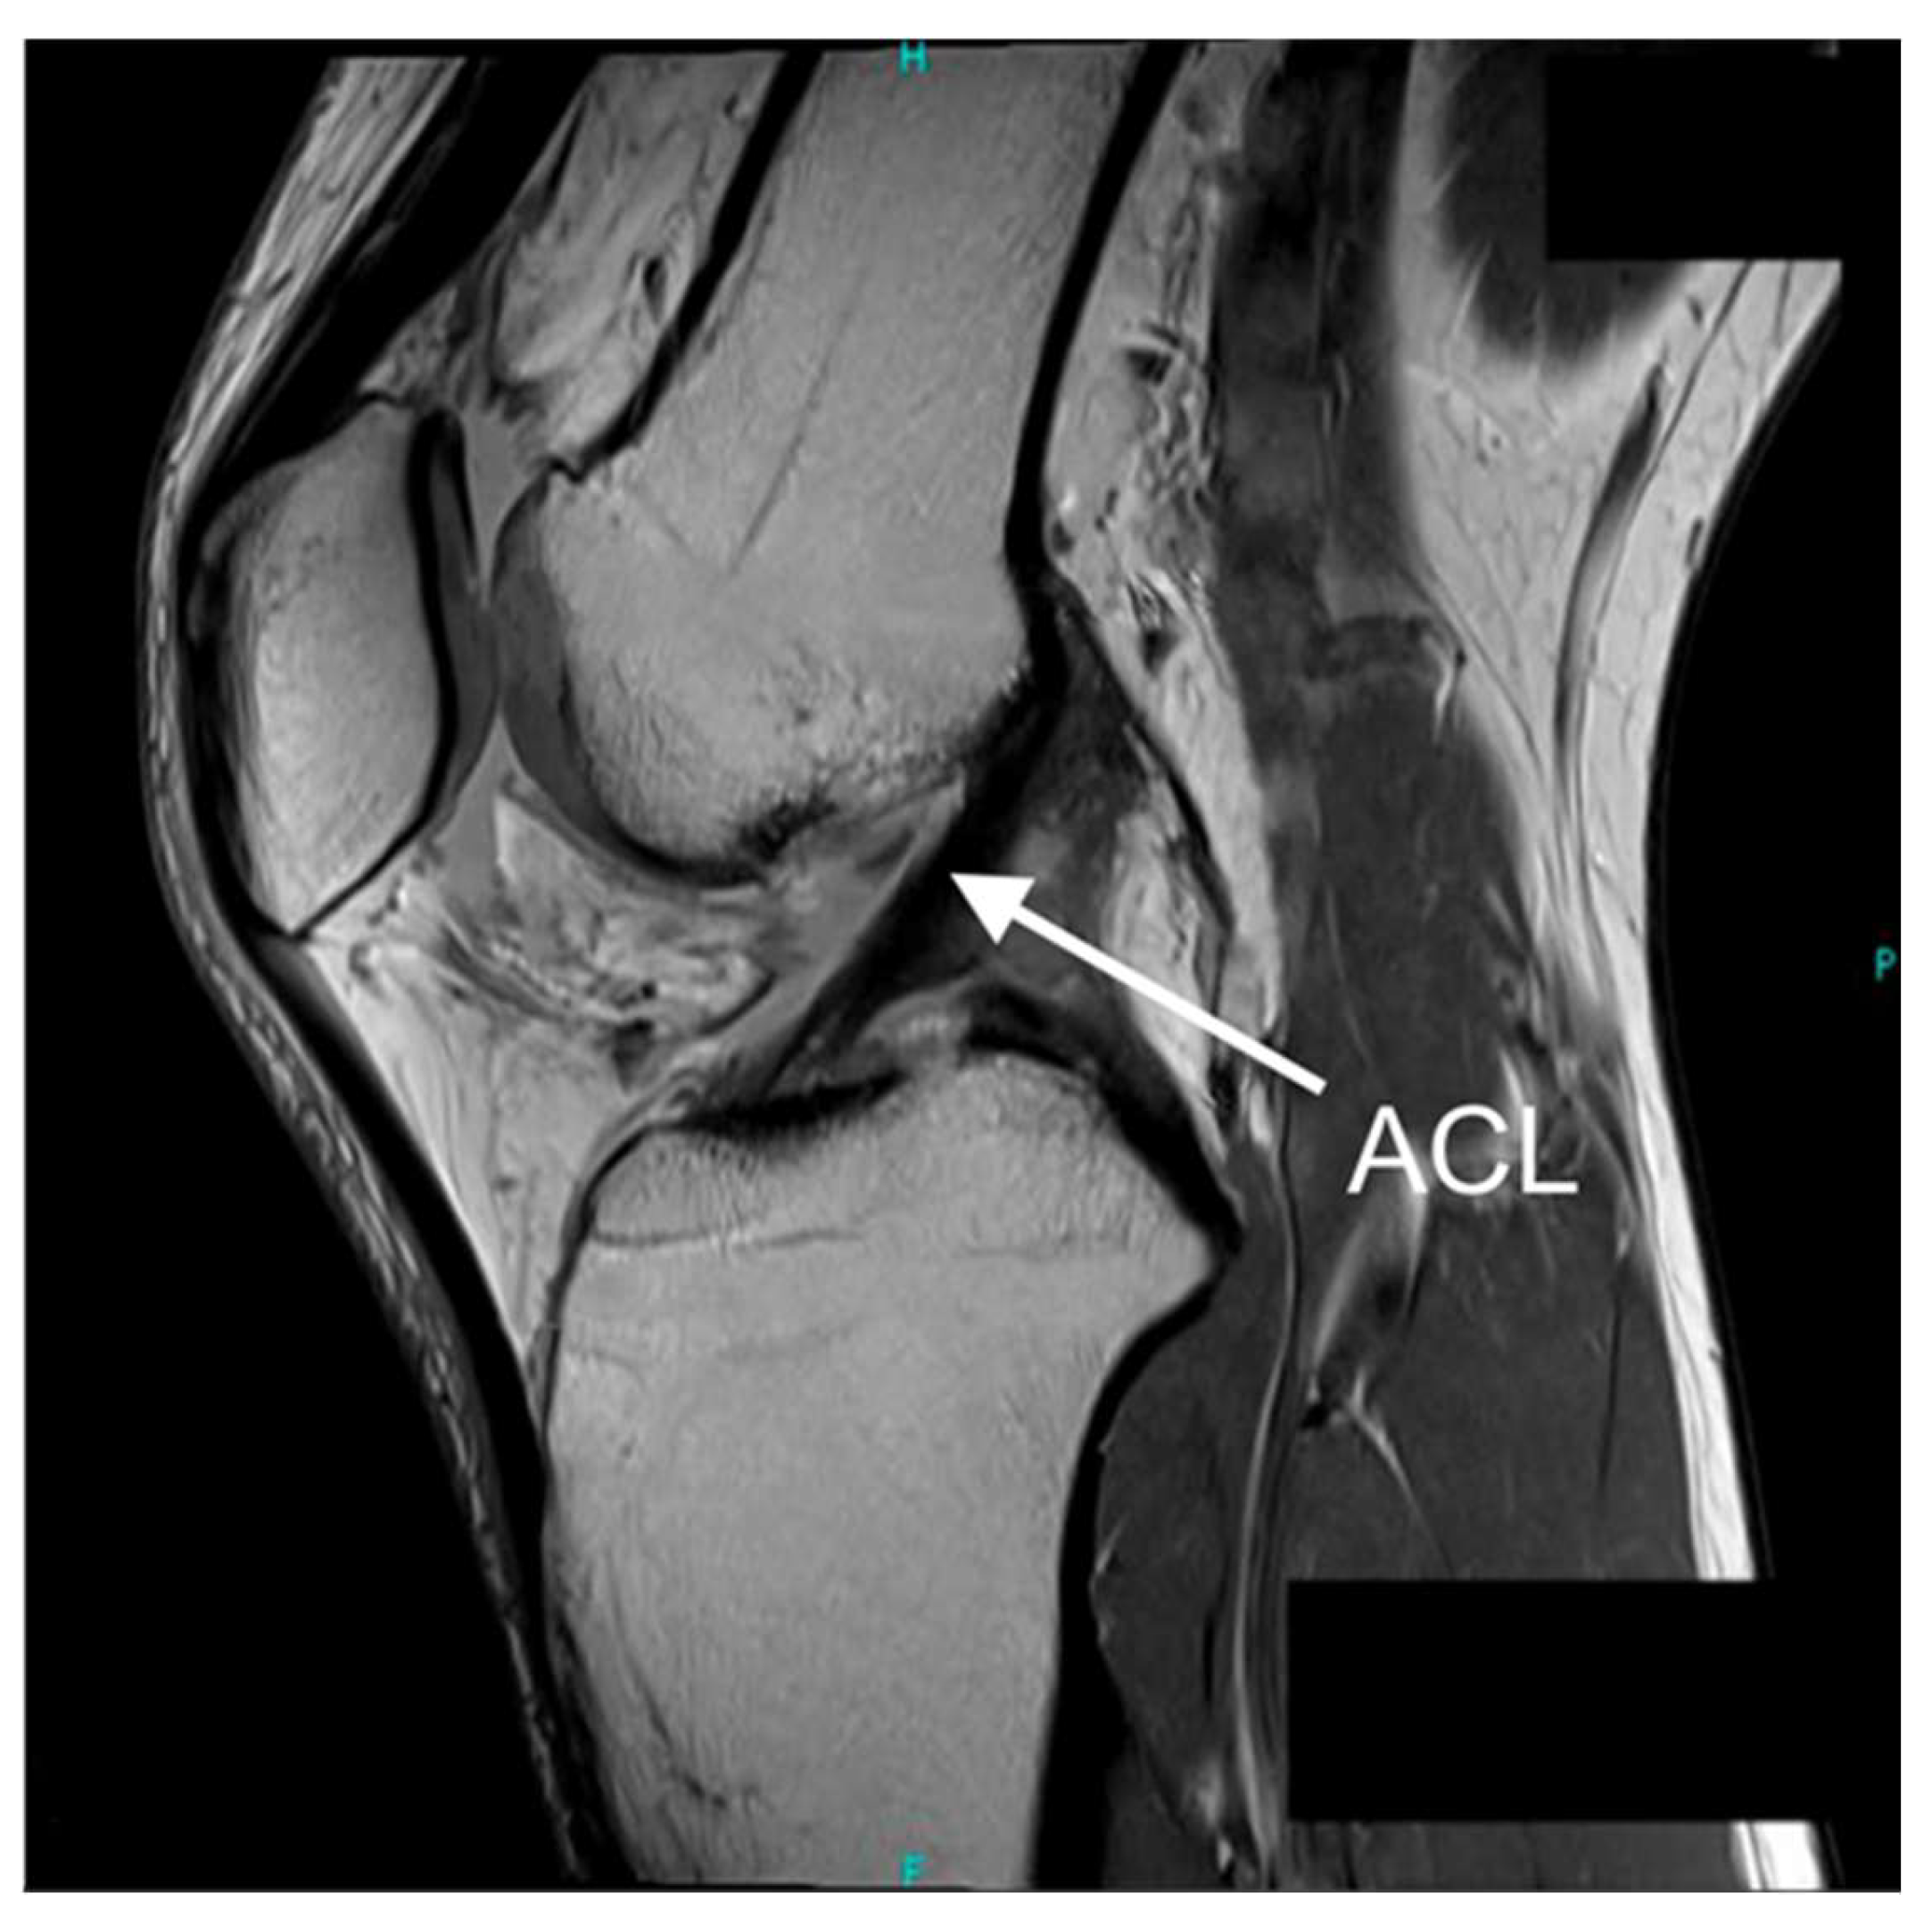

| ACL | Anterior Cruciate Ligament |